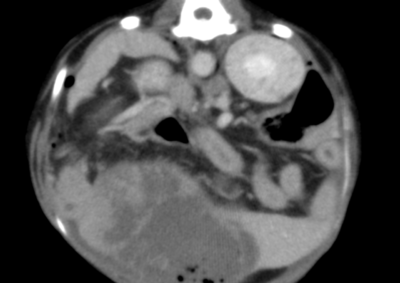

胆嚢破裂に対する胆嚢摘出術〜空腸栄養カテーテル設置